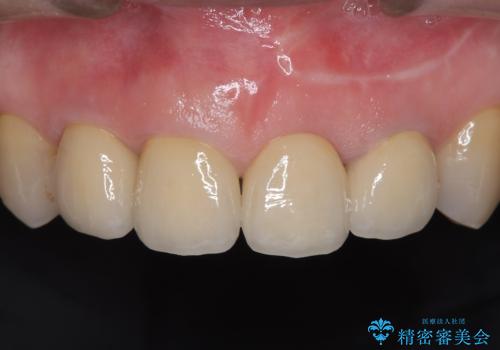

前歯4本のセラミック治療|抜歯即時インプラント+歯根端切除術で機能と美しさを回復